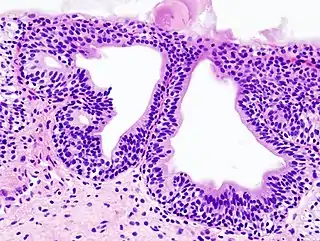

![]() Histopatología de una cistitis glandular en una biopsia citoscópica. Tinción con hematoxilina y eosina. | ||

Puede tener distintas causas. La causa más frecuente de cistitis es la infección por bacterias gram negativas, destacando entre todas la Escherichia coli. Para que un germen produzca cistitis primero debe colonizar la orina de la vejiga (bacteriuria) y posteriormente producir una respuesta inflamatoria en la mucosa vesical. A esta forma de cistitis se le denomina cistitis bacteriana aguda. Afecta a personas de todas las edades, aunque sobre todo a mujeres en edad fértil o a ancianos de ambos sexos. Otras formas de cistitis son la cistitis tuberculosa (producida en el contexto de una infección tuberculosa del aparato urinario), la cistitis química (causada por efectos tóxicos directos de algunas sustancias sobre la mucosa vesical, por ejemplo la ciclofosfamida), la cistitis rádica (secuela crónica de tratamientos con radioterapia sobre la pelvis), la cistitis glandular (una metaplasia epitelial con potencialidad premaligna) o la cistitis intersticial (una enfermedad funcional crónica que cursa con dolor pélvico, urgencia y frecuencia miccional).